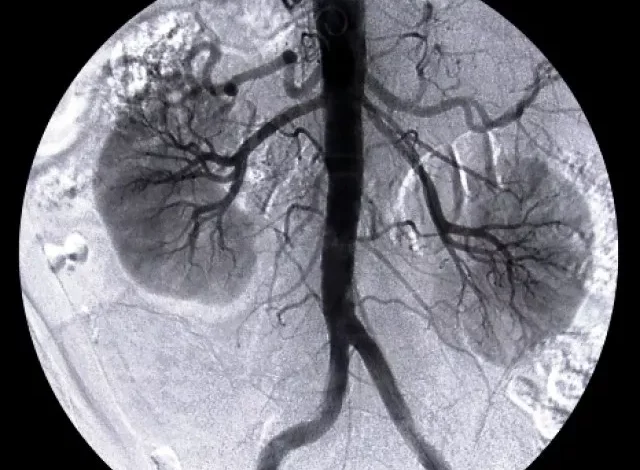

The Bahawalpur Institute of Nuclear Medicine and Urology (BINUQ) has announced that it is set to resume kidney transplantation services, marking a major step forward in providing advanced healthcare facilities to patients in the region. The program had been temporarily halted due to regulatory, logistical, and resource-related challenges, leaving many patients dependent on dialysis or forced to travel long distances for treatment.

With the resumption of transplantation, BINUQ aims to offer a lifeline to patients suffering from end-stage renal disease, a condition that has been steadily rising in Pakistan due to diabetes, hypertension, and other chronic illnesses. Hospital officials confirmed that specialized teams of urologists, nephrologists, and transplant surgeons have been prepared to ensure safe and successful procedures.